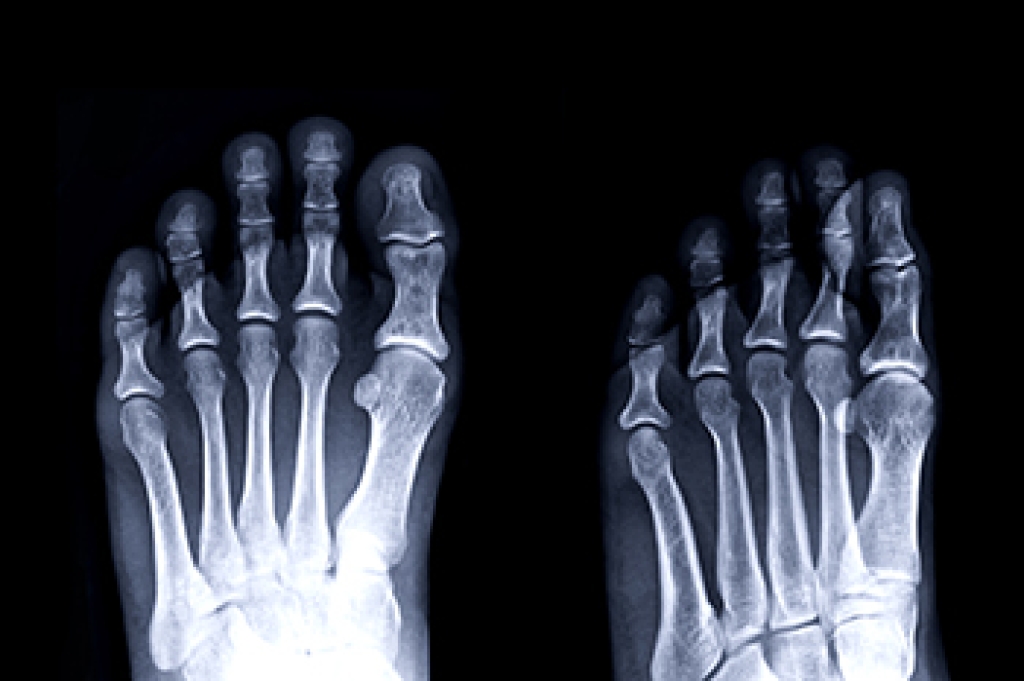

The fifth metatarsal is the long bone on the outer edge of the foot that connects to the little toe. Fractures in this bone are common and often occur from twisting the foot, direct impact, or overuse. There are two main types of fractures in this area. An avulsion fracture happens when a small piece of bone is pulled off by a tendon or ligament. A Jones fracture is more serious and occurs further along the bone, often requiring more time to heal. Symptoms include pain, swelling, bruising, and difficulty walking. Immediate care includes rest, elevation, and avoiding pressure on the foot. Some cases heal with wearing supportive footwear, while others may need a cast or even surgery. If you suspect you have injured the outside of your foot or feel sharp pain when bearing weight, it is suggested that you visit a podiatrist for a proper diagnosis and recovery plan.

A broken foot is caused by one of the bones in the foot typically breaking when bended, crushed, or stretched beyond its natural capabilities. Usually the location of the fracture indicates how the break occurred, whether it was through an object, fall, or any other type of injury.

Treatment for broken bones varies depending on the cause, severity and location. Some will require the use of splints, casts or crutches while others could even involve surgery to repair the broken bones. Personal care includes the use of ice and keeping the foot stabilized and elevated.